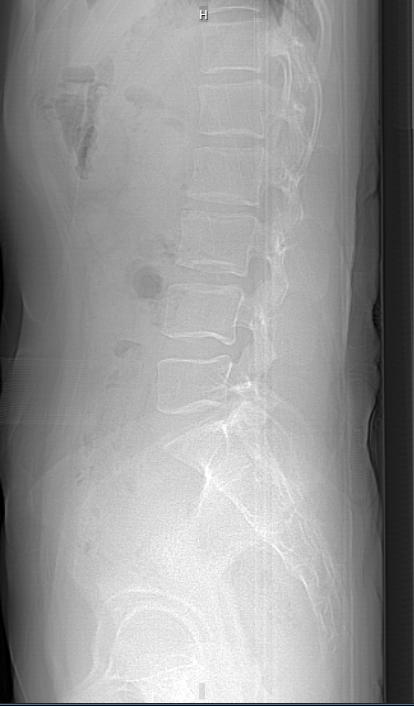

4 9 岁女性患者因工作原因患上了腰突症,检查报告提示腰椎生理曲度变直, 腰 5- 骶1 椎间盘局限性向后突出,硬膜囊受压,骨性椎管无狭窄,有骨质增生。查看舌苔,舌淡红,苔薄白,属于脾虚,气血不足。